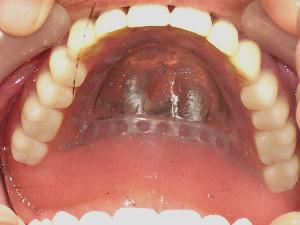

金属義歯とは、入れ歯の主要部分を金属で作った入れ歯です。 レジン(プラスティック)に比べて丈夫な素材である金属を使うため、快適で、たわまず、丈夫な入れ歯を作ることが可能になります。 金属ならではの薄い仕上げは違和感を少なくし、お口の中を広く感じさせ、熱の伝わりの良さで一層おいしく食事を楽しむことができます。 |

薄くて快適:保険の義歯の約1/3の薄さで入ればを作ることが可能です。 温度が伝わる:食べ物の温度を瞬時に伝えることができます。 歯にも優しい:部分入れ歯でも残っている天然歯にあまり負担を掛けません。 引用元:「快適な入れ歯のご案内」Wada Precision Laboratories Co.,Ltd. 部分入れ歯を固定するためのバネを目立たないように仕上げることができます。 前歯に入れ歯の大きなバネが見えることに抵抗がある方にはお勧めです。 修理、リフォームも可能です。 「義歯の料金」の詳細はこちら